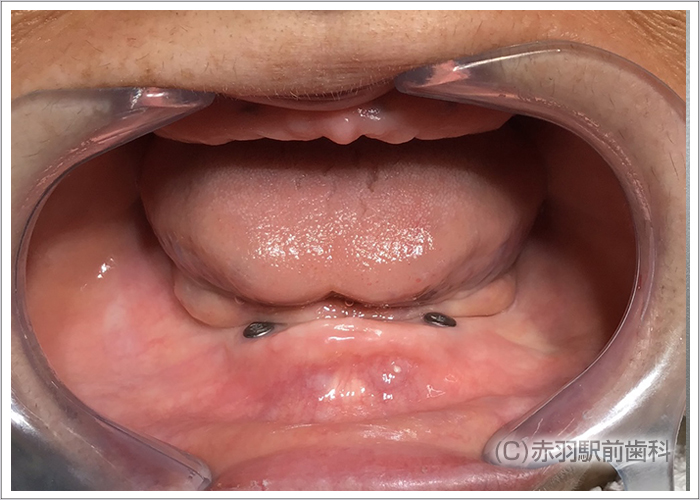

歯を全て失った患者様です。上下とも総入れ歯を入れていました。入れ歯が安定しないので食べるものも制限され会話もしづらい状態です。

CTデータから事前に3Dプリンターで、患者様の実寸代の顎骨模型を作成しておいて手術前にシミュレーションで担当医がインプラント埋入とSRAアバットを装着しておきました。画像は下顎の模型です。両サイドのインプラントはオールオン4特有の傾斜埋入をしてあります。

シミュレーション通りの位置にインプラント手術を完了しました。上下ともに両サイドのインプラントはオールオン4特有の傾斜埋入をしています。

インプラント手術完了後にSRAアバットを装着した状態の口腔内です。固定式の仮歯が当日に入ります。